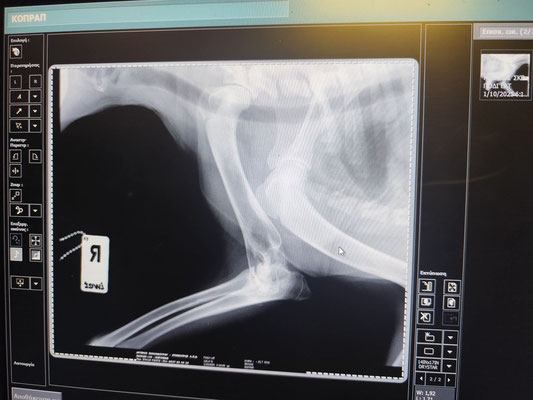

Clara wurde am Bahnhof gefunden, wo sie gemeinsam mit einem Rudel streunender Hunde lebte. Ihr rechtes Vorderbein war, wie sich herausstellte, gebrochen, weshalb sie jetzt beim Gehen leicht hinkt.

Sie wurde in dieser Woche bei einem Orthopäden vorgestellt. Dieser riet dazu, keine Operation durchführen zu lassen, da Clara ihr Bein gut benutzt und nur leicht hinkt. Eine Versteifung (Arthrodese) wird nicht empfohlen.